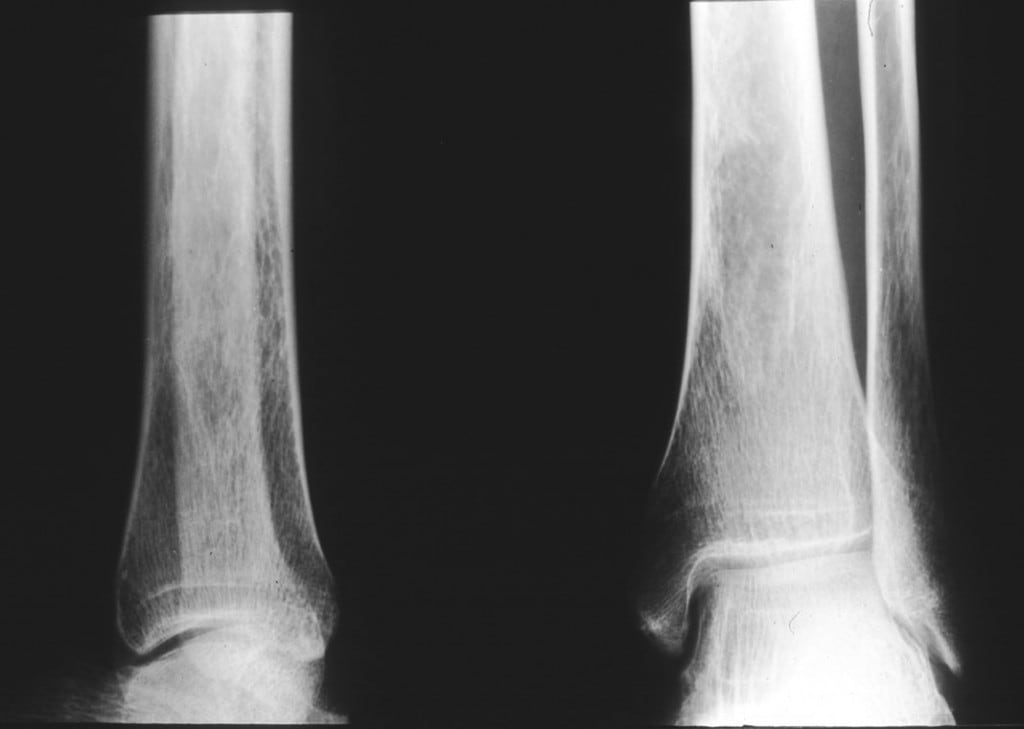

The bone densities of heel, small finger and upper jaw were measured at baseline then at 4, 12 and

“The bone density of the heel measured by the Sahara densitometer remarkably improved in the Meriva-supplemented group, with a significant decrease of ultrasounds transmission values at week 12 (-18.4%) and at week 24 (-21.0%), compared with baseline values,” wrote the authors.

Furthermore, the bone densities of small finger and upper jaw also significantly increased during the study in supplemented subjects, reaching +7.1% and +4.8%, respectively, at week 24 compared with baseline.